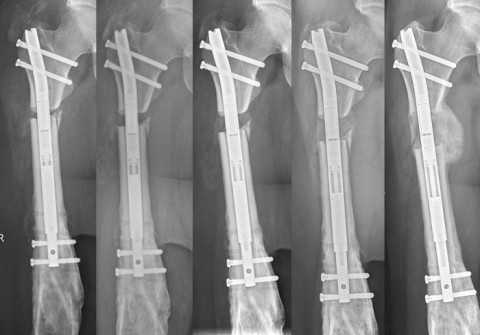

Aufgrund der nun noch persistierenden Beinlängendifferenz entschlossen wir uns zu einer Verlängerung des Oberschenkelknochens mit dem magnetgetriebenen Precice®-Marknagel. So konnten wir den Oberschenkel schlussendlich mit diesem Nagel problemlos um 3.5 cm verlängern (Bild 3).

Wir beginnen mit der Knochenverlängerung üblicherweise am 7. bis 10. Tag nach der Operation. Zu diesem Zeitpunkt ist der Patient meistens bereits aus der Spitalpflege entlassen und führt die Knochenverlängerung selbständig zu Hause durch. Üblicherweise beträgt die Verlängerungsgeschwindigkeit 1 mm pro Tag, kann aber je nach Verlauf problemlos variiert werden.

Eine anfängliche Teilbelastung an Gehstützen mit 10-15 kg ist sinnvoll, später können die Nägel auch mit vollem Körpergewicht belastet werden. Anfängliche postoperative Schmerzen minimieren sich im Verlauf, die Verlängerung ist üblicherweise nicht schmerzhaft. Erst ab etwa 3 cm Verlängerung wird der Muskelzug etwas unangenehm, eine begleitende Physiotherapie ist in jedem Fall immer erforderlich. Der Nagel wird üblicherweise ein Jahr nach der Verlängerung entfernt.